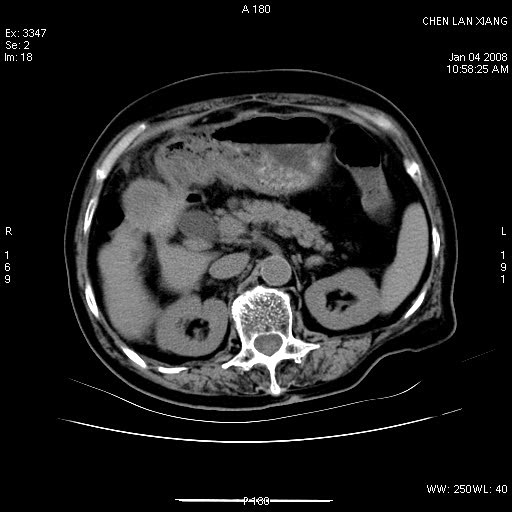

女,76岁,腹痛3-4天,b超示:肝内实性肿物,胆囊强回声,胆总管扩张.

考虑:1、胆总管下端结石伴梗阻性肝内外胆管扩张(肝左叶外侧段肝内胆管多发结石、胆管炎);

胆总管及肝内胆管扩张

1 胆总管末端结石伴肝内胆管结石,肝内外胆管扩张。2 胆囊扩大,胆囊壁不规则增厚,内见软组织密度影。考虑:慢性胆囊炎,不除外胆囊癌!

胆总管及肝内胆管多发性结石并扩张。

ct所见:1、 肝内胆管结石,肝内外胆管扩张。低位胆道梗阻,胆总管下端结石;2 胆囊扩大,胆囊壁不规则增厚

考虑:胆总管下端结石并肝内外胆管扩张,肝内胆管结石;